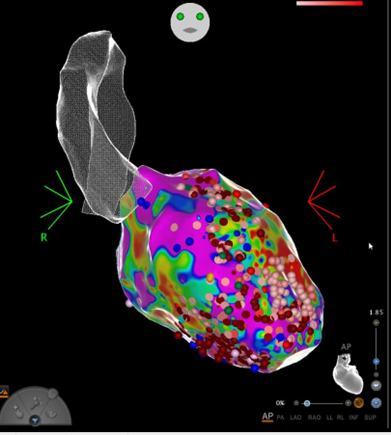

In our special consultation hours, we create a personal treatment strategy for each patient together with the resident doctors. After an initial attempt to control the rhythm with medication, and in some cases even before that, catheter ablation has established itself as the method of choice for treating atrial fibrillation. In the case of paroxysmal atrial fibrillation and the absence of structural heart disease, 70-90% of patients can be treated successfully. In patients with heart failure, it has even been shown that catheter ablation of atrial fibrillation can increase the probability of survival. Basically, the earlier the treatment, the higher the chances of success. Our center uses state-of-the-art methods using CT (Fig. 1) and MRI, fusion procedures with moving fluoroscopic images and 3D mapping systems.